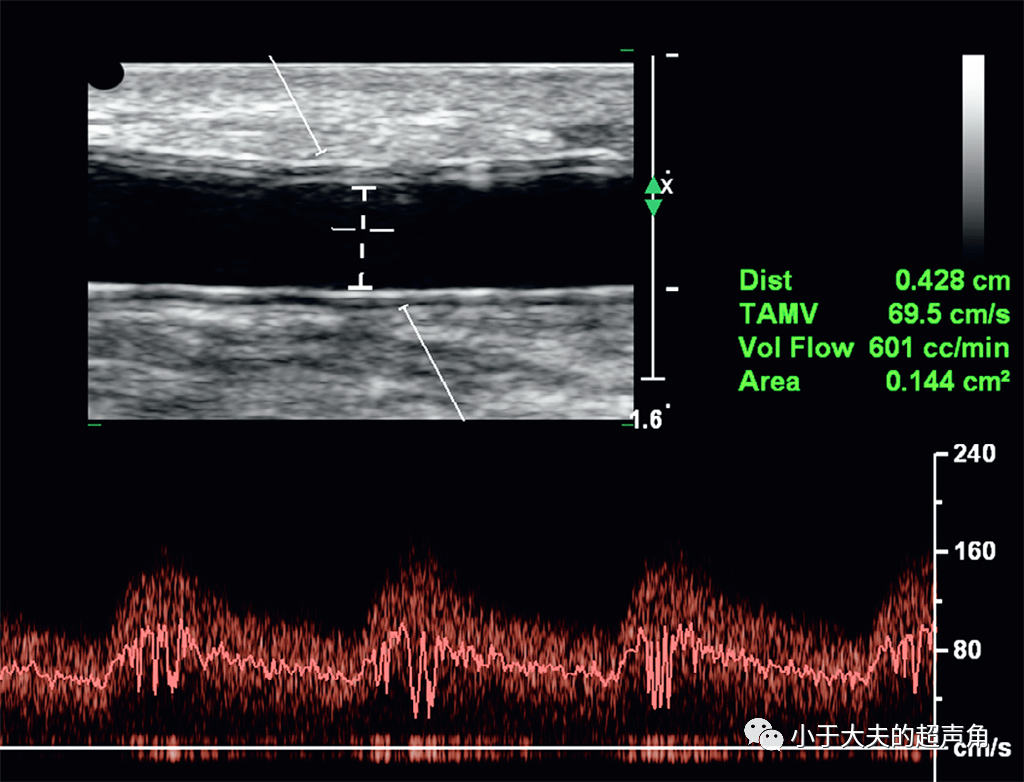

该如何用超声来评估动静脉瘘呢它能造瘘吗它成熟了吗它有狭窄吗